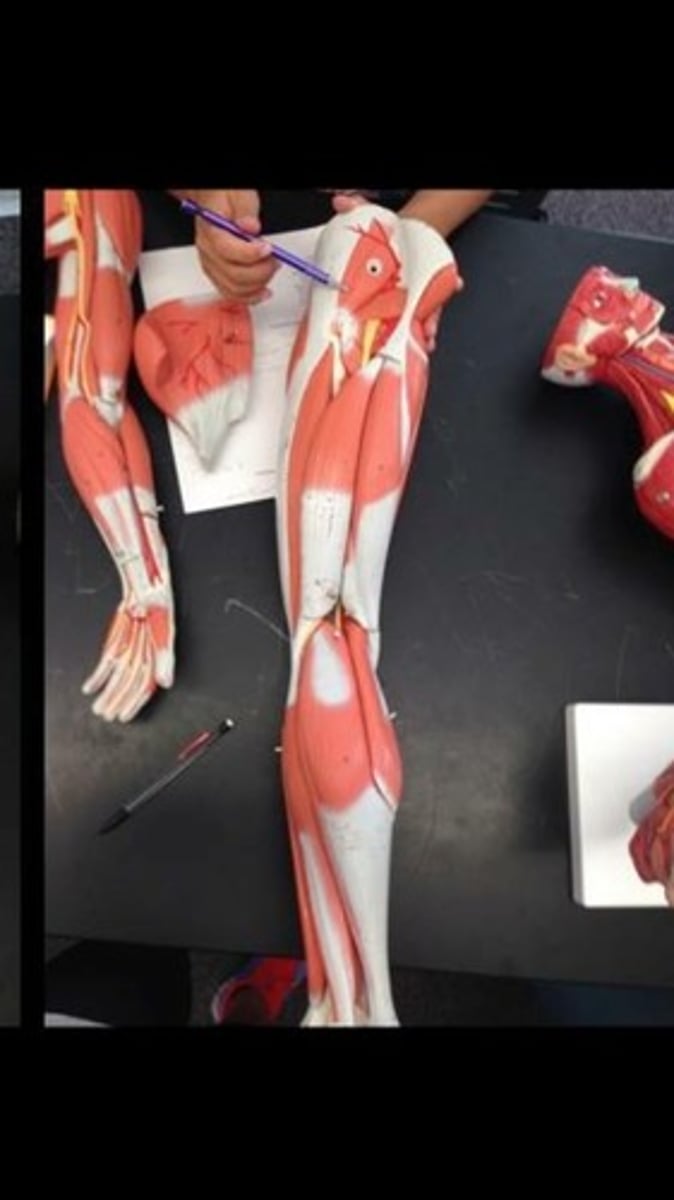

Skeletal muscle terms and structure

114 Terms

Rectus femoris

Vastus lateralis

Vastus intermedius

Vastus medialis

Sartorius

Semimembranosus

Semitendinosus

Biceps femorus longhead

Biceps femorus shorthead

Gastrocnemius lateral head

Gastrocnemius medial head

Soleus